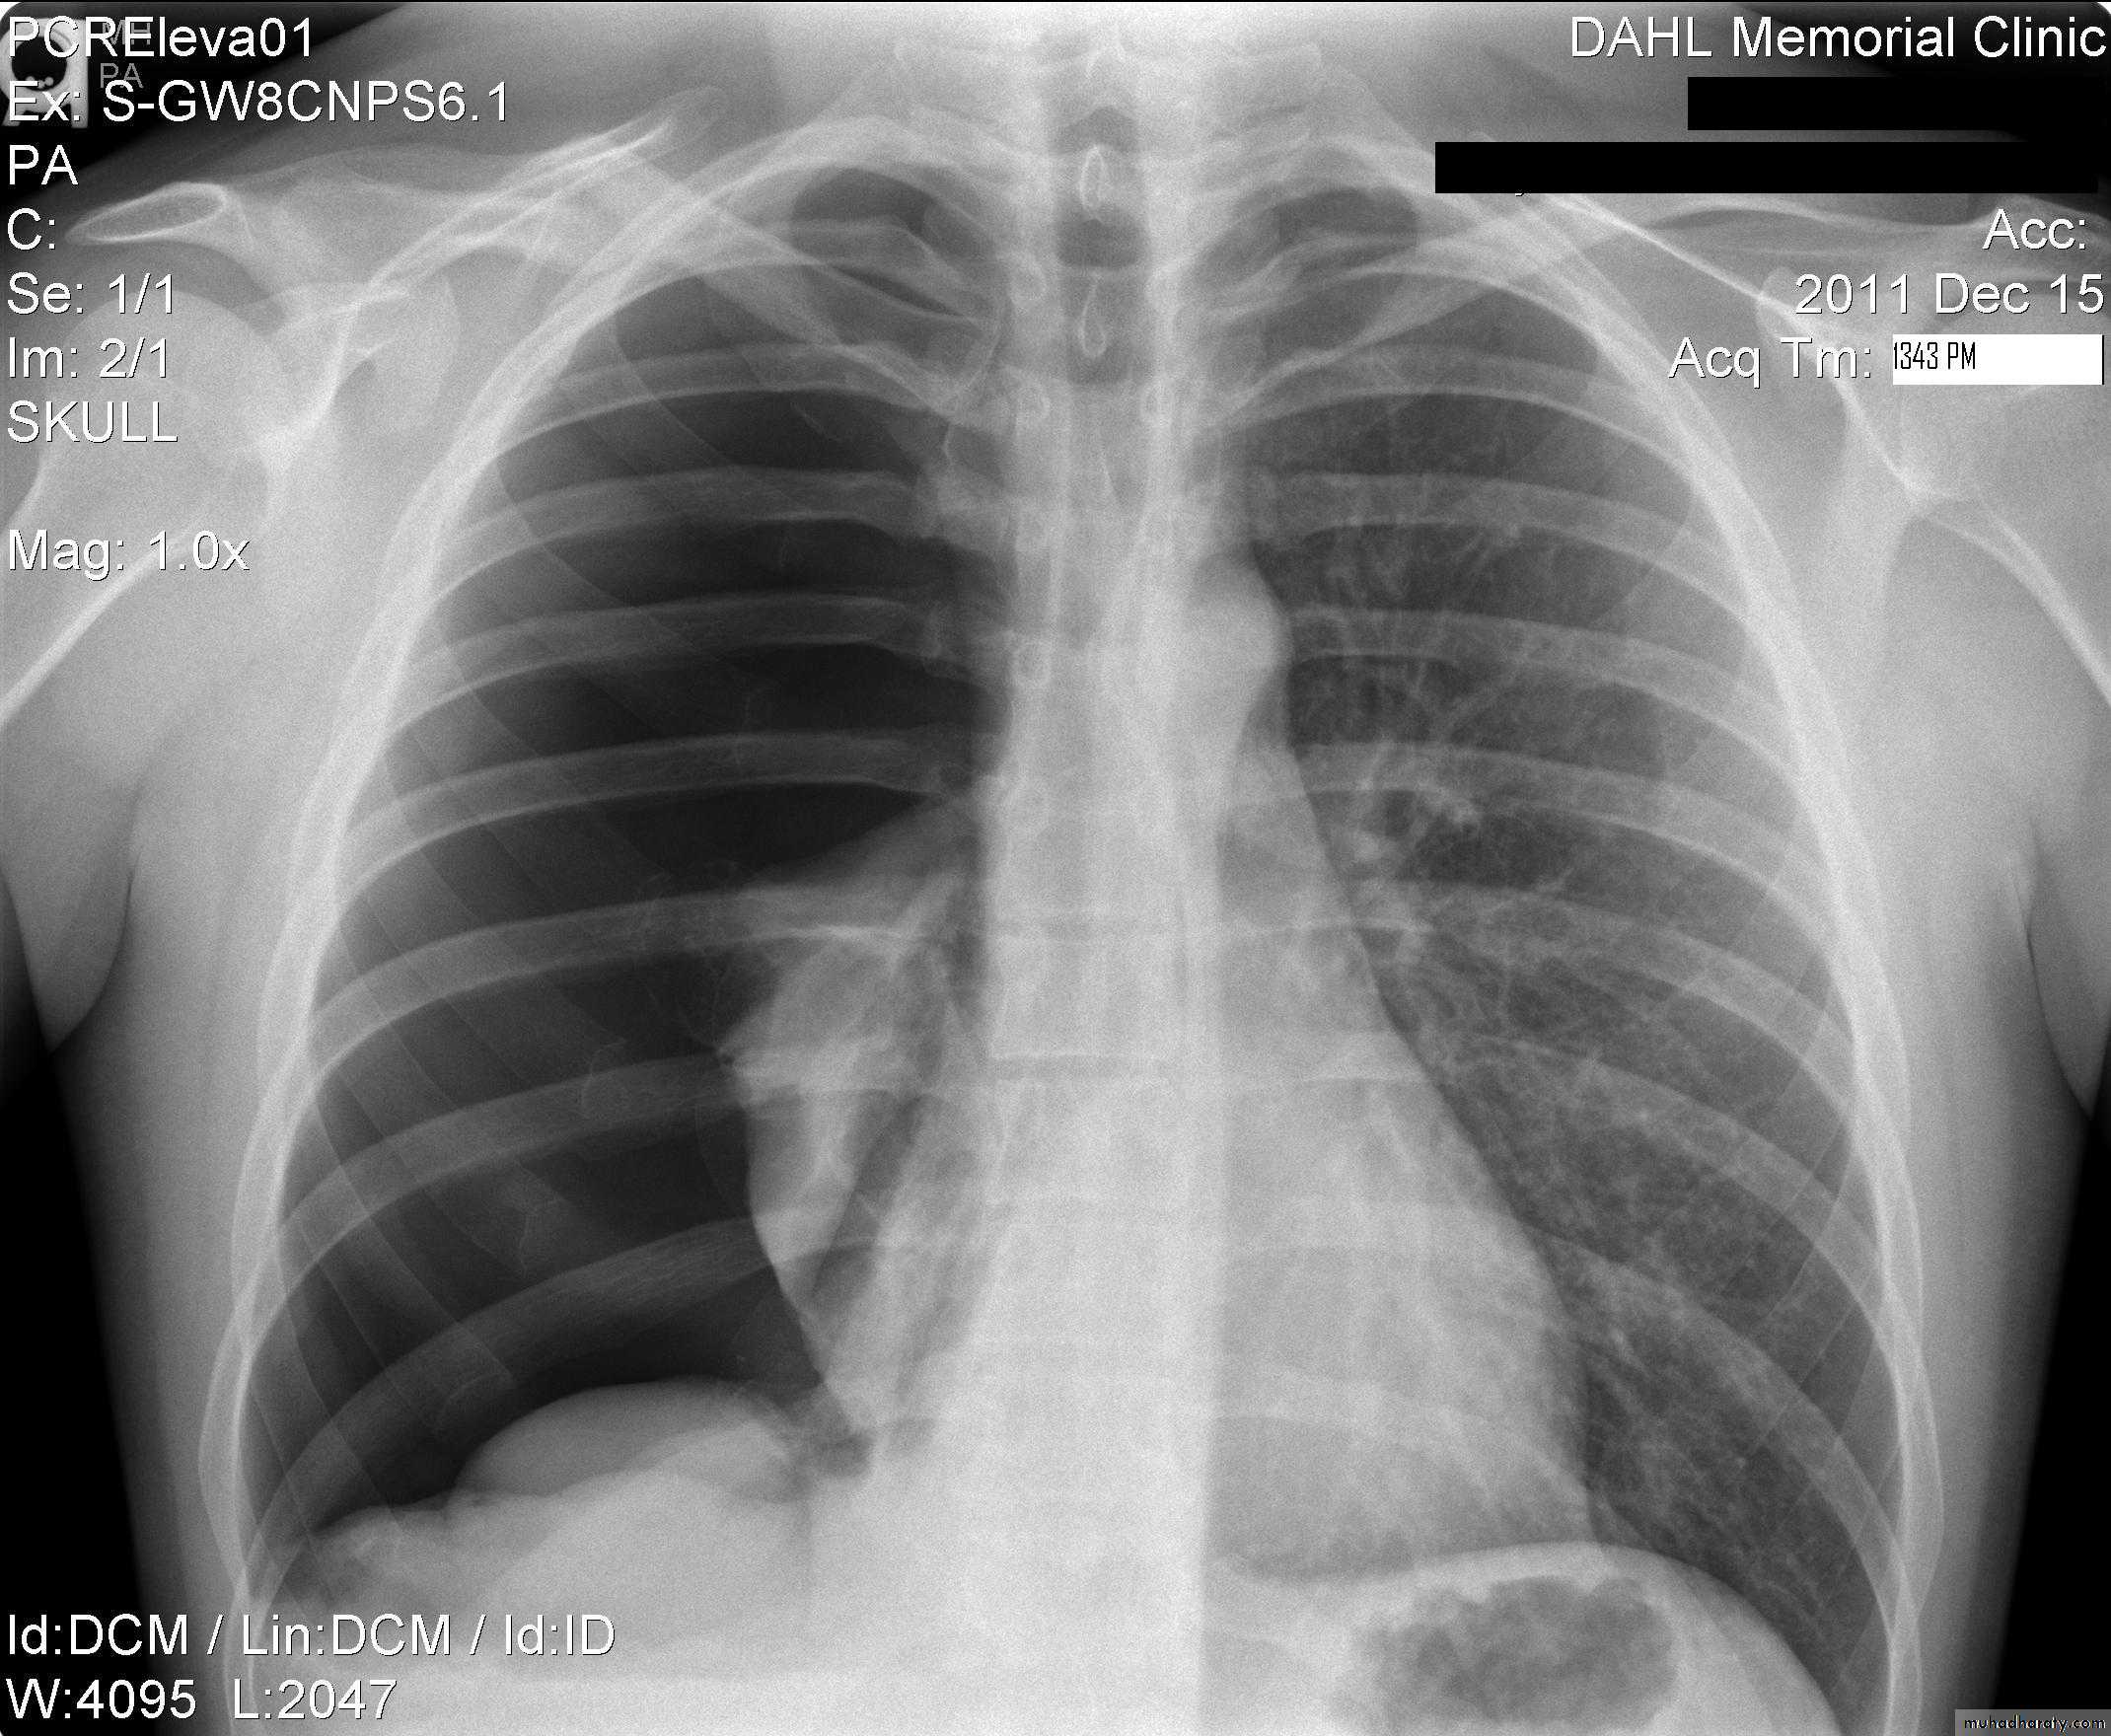

Normal chest XR PA & lateral view

Look carefully on both diaphragmatic cruse costo & cardio phrenic angles

Don't forget to use rib in asses lung Zones

1,2,3 .presentation4.normal chest film ( PA ) view

8.normal chest XR PA & lat. view